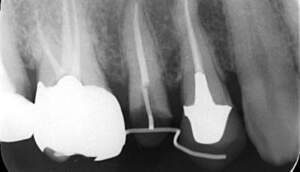

カリエスを取り除くと、遠心の歯質が歯肉縁下になりました。

MTM開始直後と、終了後です。フックの位置が変わっているのがわかると思いますが、それが歯が動いた証拠となります。

MTM中。頬側には審美面の回復のために仮歯がついています。

歯からはフック、隣り合った歯にはワイヤーが渡してあります。そこにゴムをひっかけて歯を挺出させます。